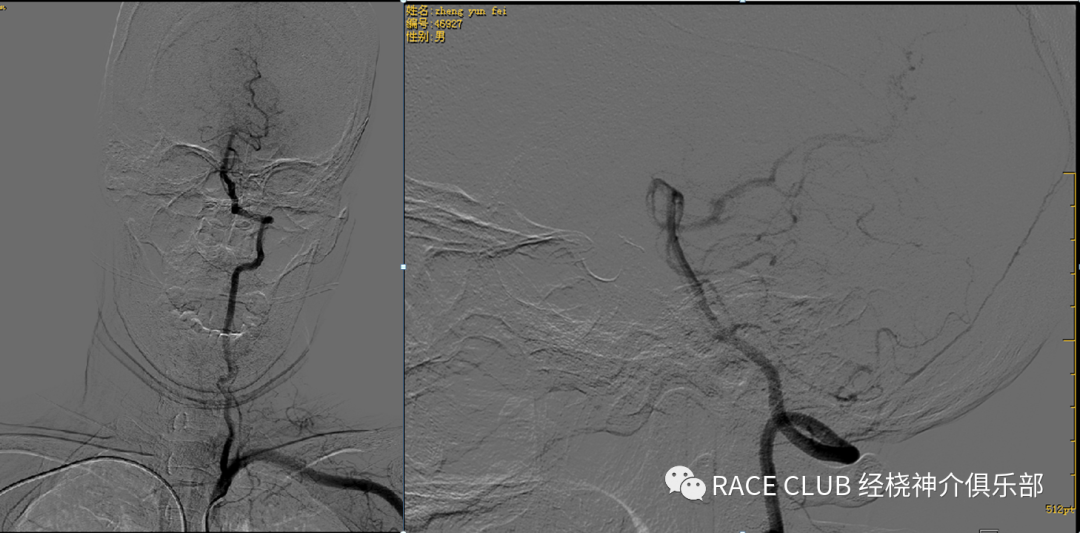

主动脉弓造影

用泥鳅导丝将猪尾导管导入升主动脉,抽出导丝,接注射器

摆好位置,一般左斜45°,下端露出导管头

接高压连接管

注意看弓形态、各个开口大致位置、走形,特别注意右侧锁骨下动脉

弓上造影(股动脉入路)

接三通、y阀,排气 •接上单弯导管或西蒙导管排水

•透视下推床,露出升主动脉

•进泥鳅导丝,将猪尾导管头端拉直,一起退出

•将单弯导管或西蒙导管头端送入血管鞘内,泥鳅导丝浸水后从y阀送入,透视下将导管导入,分别进入右锁骨下动脉、双侧颈总动脉(颈内动脉)、左锁骨下动脉造影